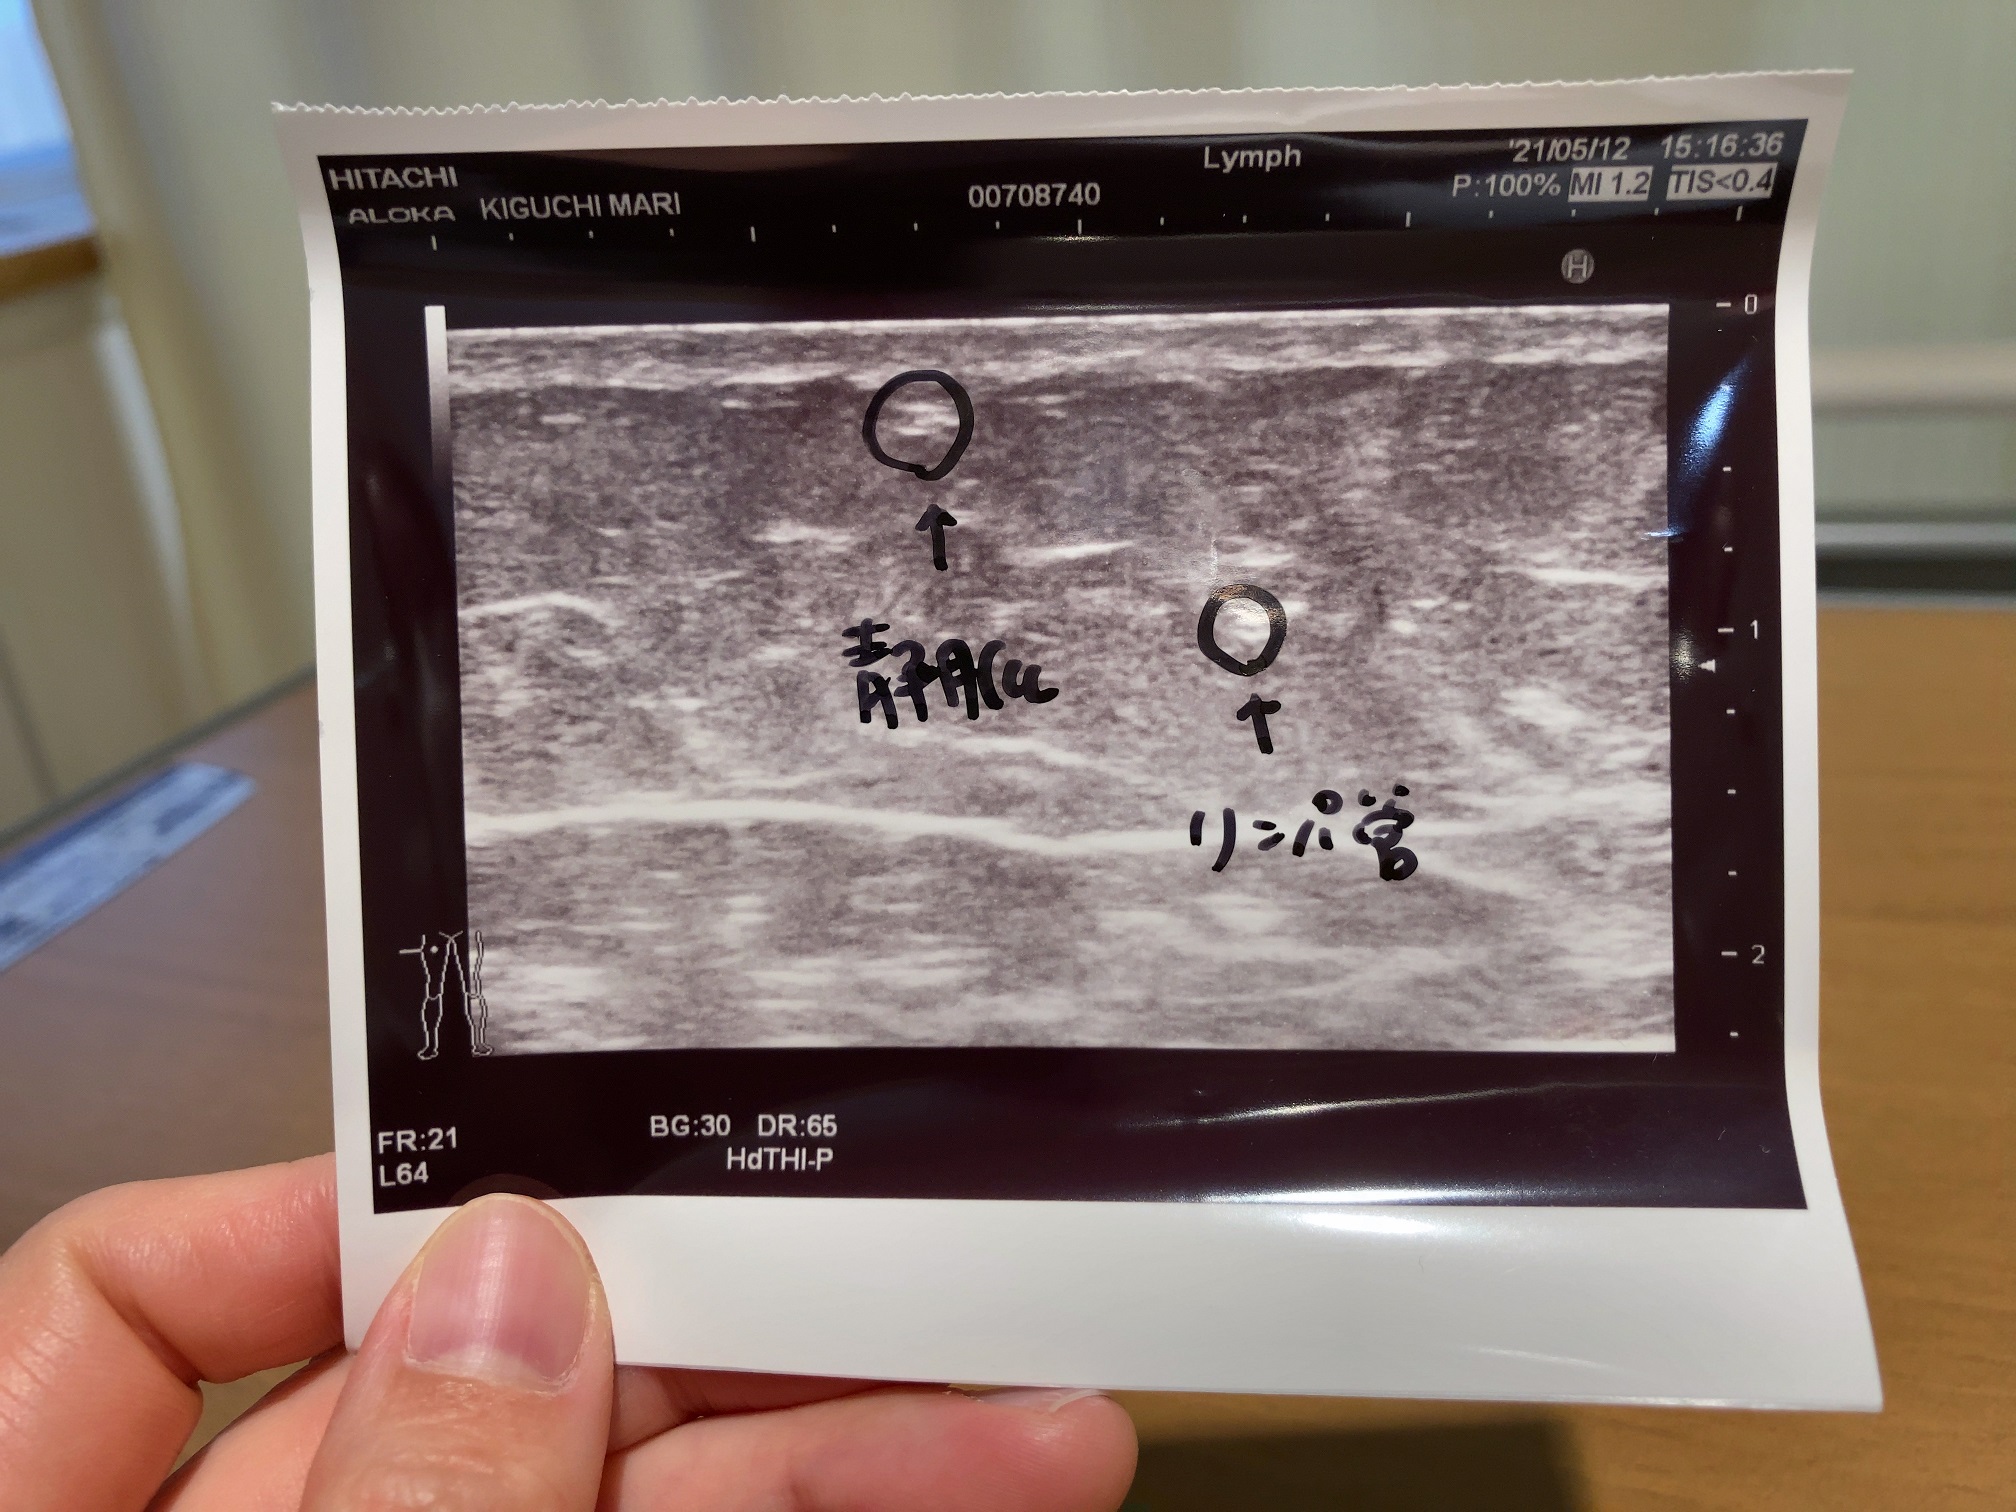

婦人科の主治医の勧めで、リンパ浮腫の専門医、三原 誠(みはらまこと)先生と原 尚子(はらひさこ)先生の診察を受けることになったキグチ。